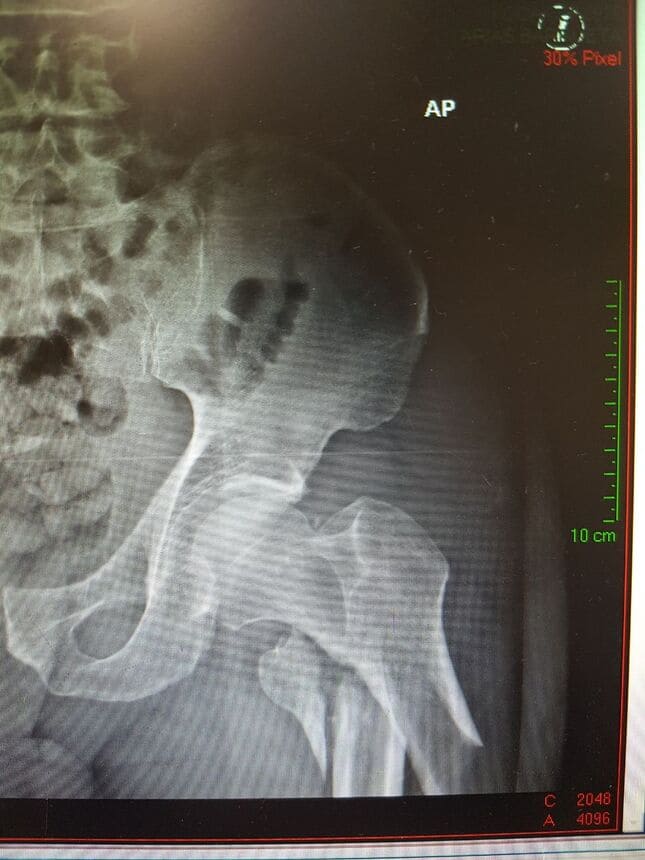

Clavo de fémur